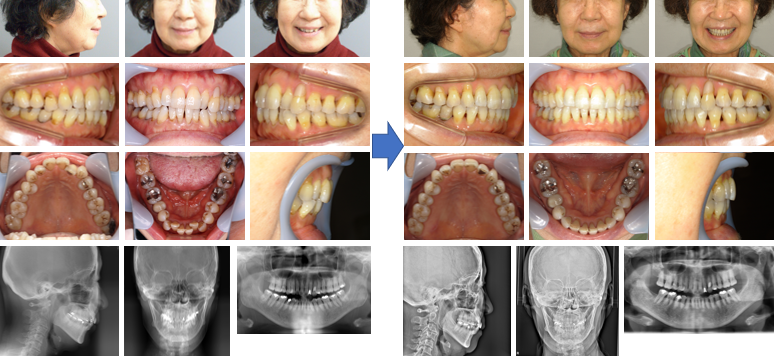

【治療例】初診時年齢:61歳0か月 / 性別:女性 / 主訴:上前歯が出てきた、下のガタガタ

治療の概要:45年前に名誉院長が上下顎両側第一小臼歯を抜歯をした症例であるが、上下顎前歯部に後戻り(叢生)が認められた。隣接歯面の削合を行いながらマウスピース型(アライナー型)矯正装置(インビザライン®)にて叢生の改善を行った。

主訴:上前歯が出てきた、下のガタガタ

診断名:上下顎両側第一小臼歯の既抜歯を行っていた後戻り症例

使用した主な装置:マウスピース型(アライナー型)矯正装置(インビザライン®)

抜歯/非抜歯および抜歯部位:非抜歯(上下顎両側第一小臼歯の既抜歯)

※こちらの症例は2022年6月から2023年11月に行った矯正です(現在も経過観察中)

治療期間:1年5か月

治療回数:22回